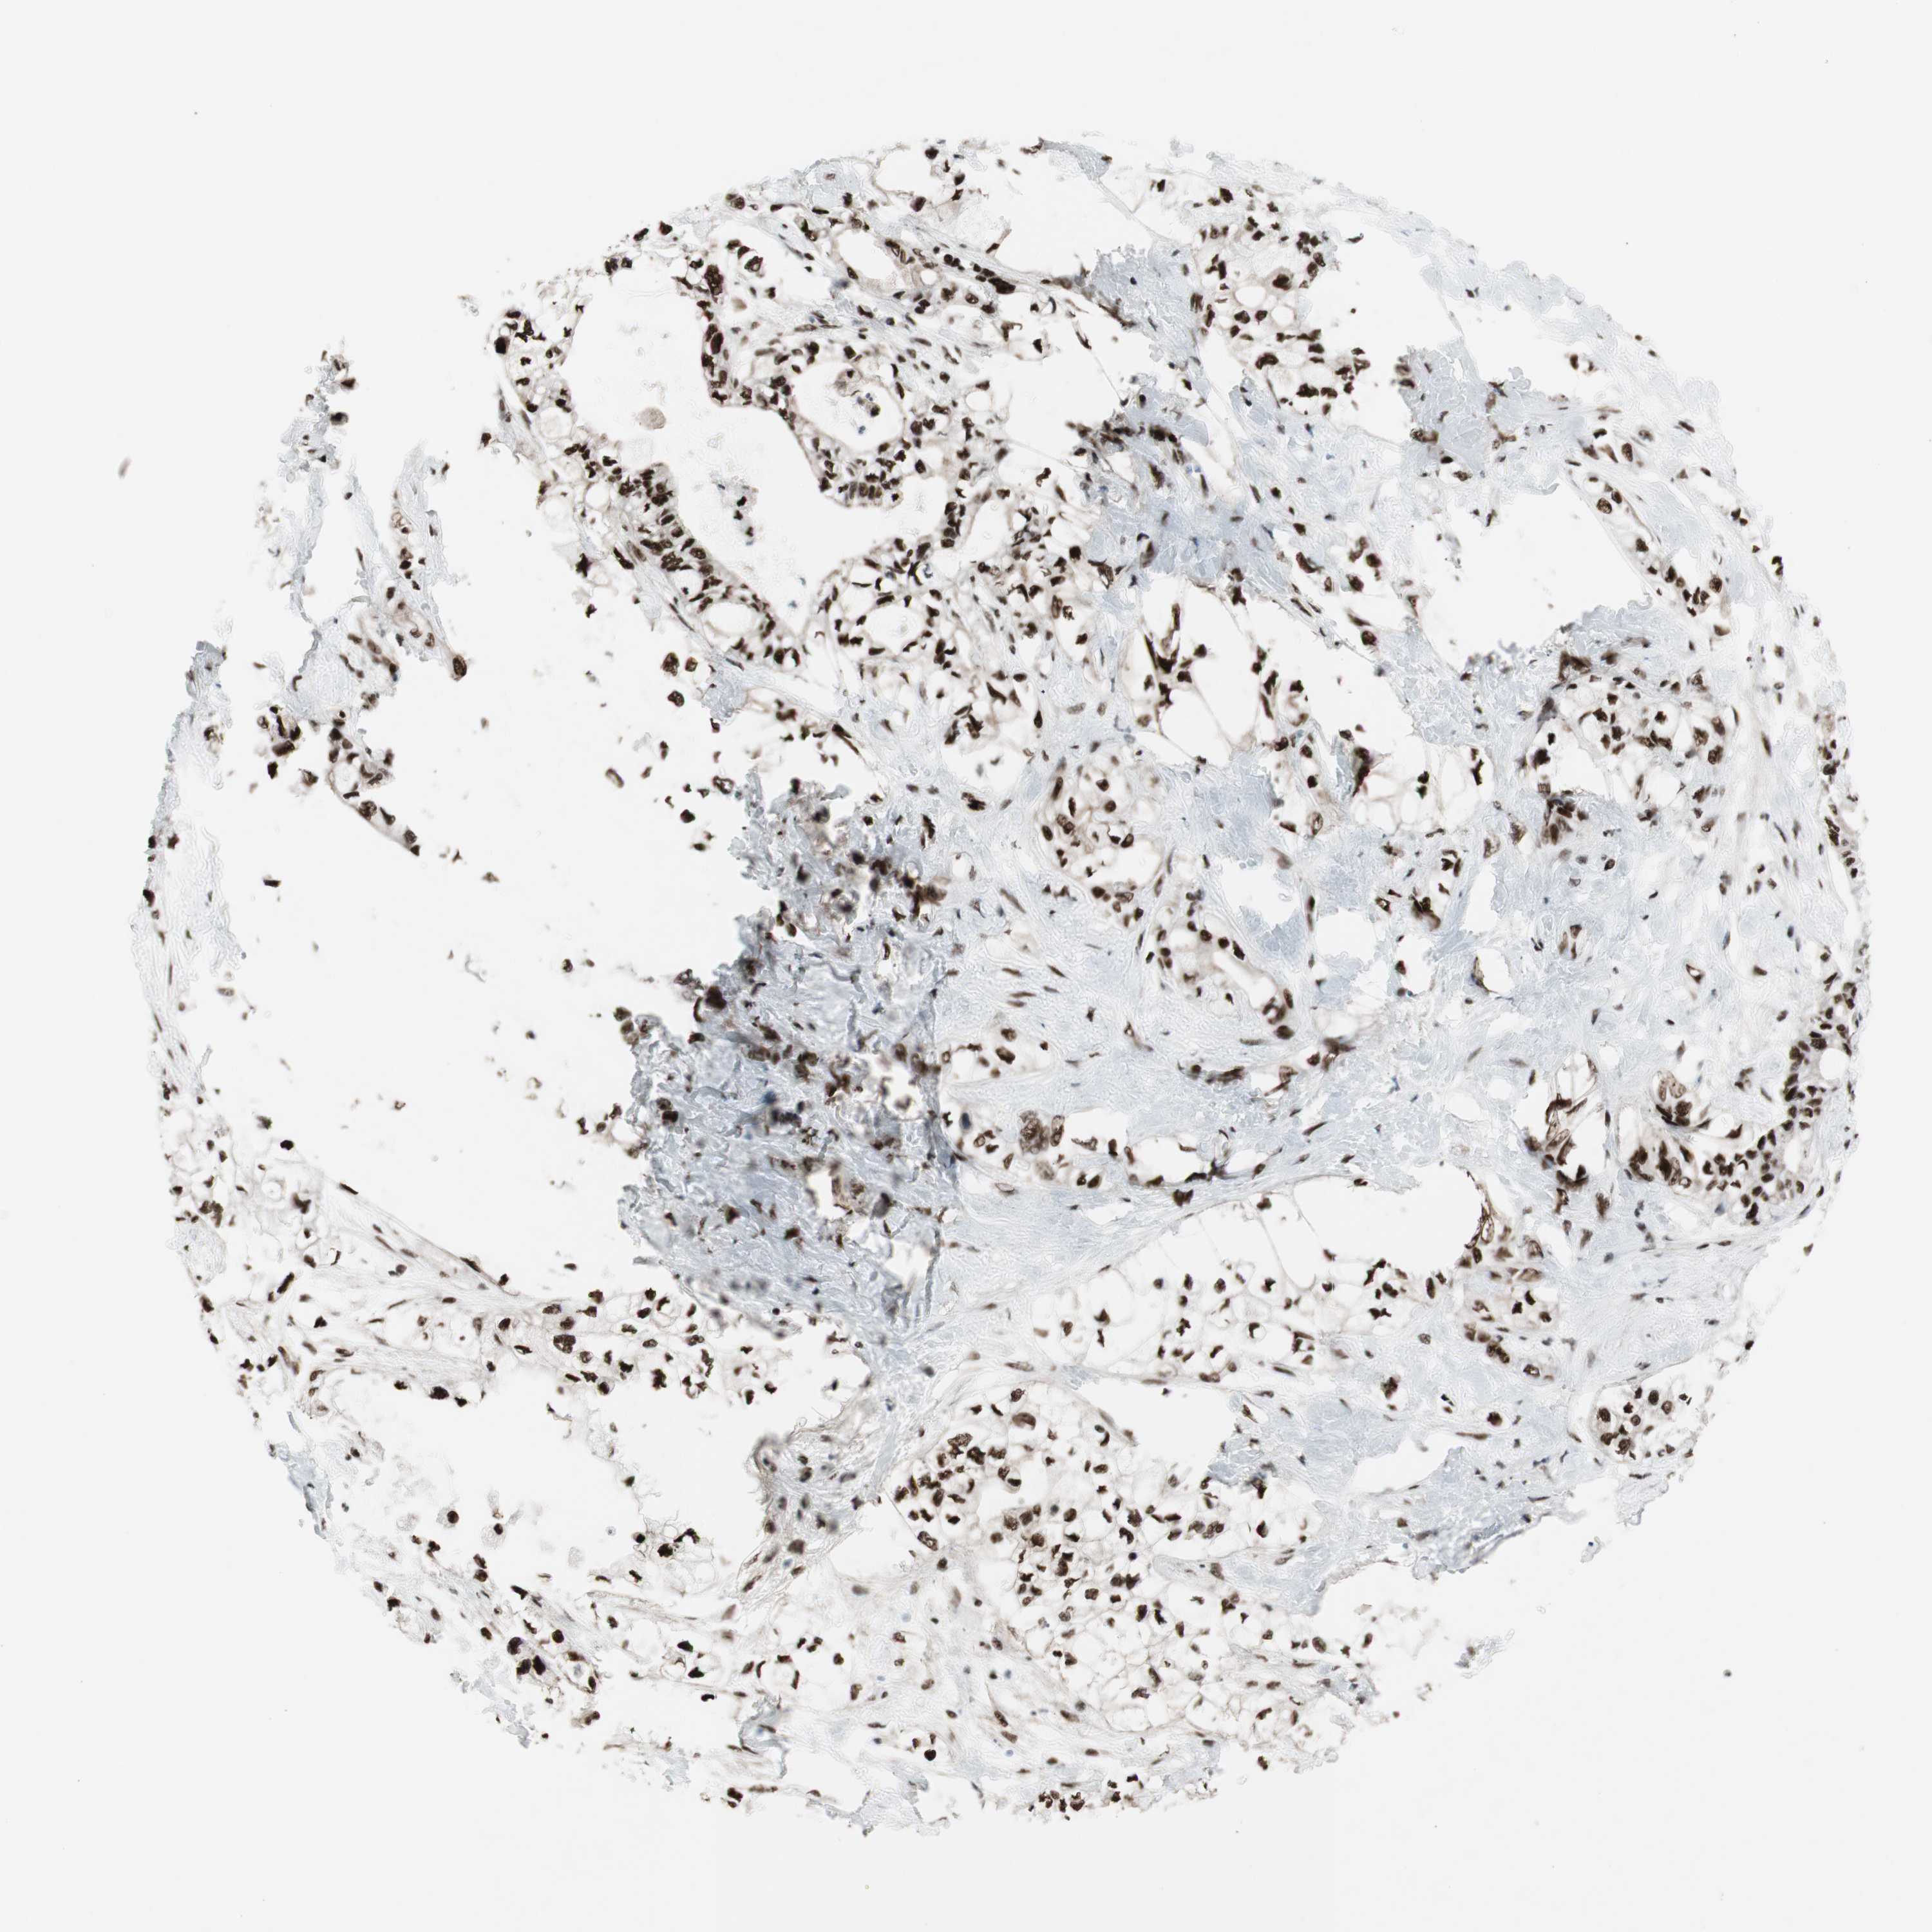

PANCREATIC CANCER - Protein expressioni

A mouse-over function shows sample information and annotation data. Click on an image to view it in a full screen mode. Samples can be filtered based on level of antibody staining by selecting one or several of the following categories: high, medium, low and not detected. The assay and annotation is described here.

Note that samples used for immunohistochemistry by the Human Protein Atlas do not correspond to samples in the TCGA dataset.

Antibody stainingi

Antibody staining in the annotated cell types in the current human tissue is reported as not detected, low, medium, or high, based on conventional immunohistochemistry profiling in selected tissues. This score is based on the combination of the staining intensity and fraction of stained cells.

Each image is clickable and will lead to virtual microscopy that enables deeper exploration of all samples and also displays staining intensity scores, fraction scores and subcellular localization as well as patient and tissue information for each sample.

Antibody CAB011625

Adenocarcinoma, NOS